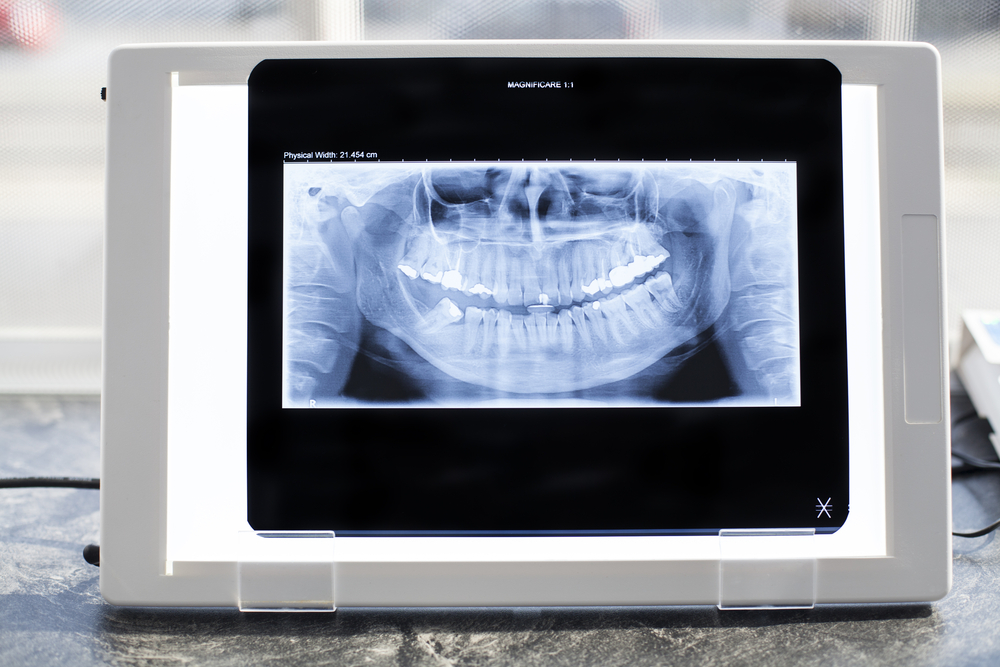

A Panorex X-ray (also called a panoramic dental X-ray) gives your dentist a single, wide view of your entire mouth, jaw, and surrounding structures—all in one image. This big-picture view helps us better understand what’s happening beneath the surface and plan your care with confidence.

Assess overall oral health by viewing all teeth, upper and lower jaws, and surrounding bone at once

Detect impacted teeth, especially wisdom teeth that haven’t erupted properly

Evaluate jaw concerns like pain, clicking, TMJ disorders, or limited mouth opening

Plan dental treatments such as braces, implants, extractions, or dentures

Identify infections or disease, including cysts, tumors, abscesses, or bone loss

Check tooth development, which is especially helpful for children and adolescents

Assess trauma, such as jaw fractures after an injury